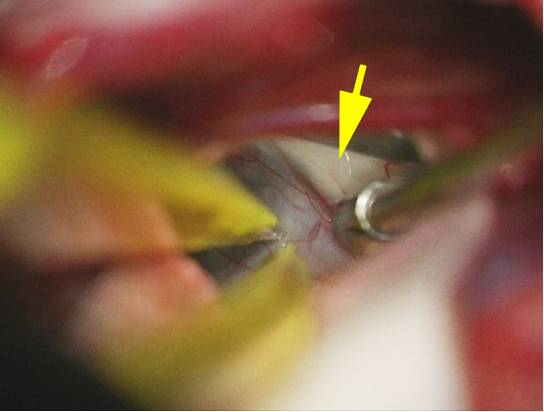

图13. 肿瘤前壁小心从穹窿柱(黄色箭头)上分离。